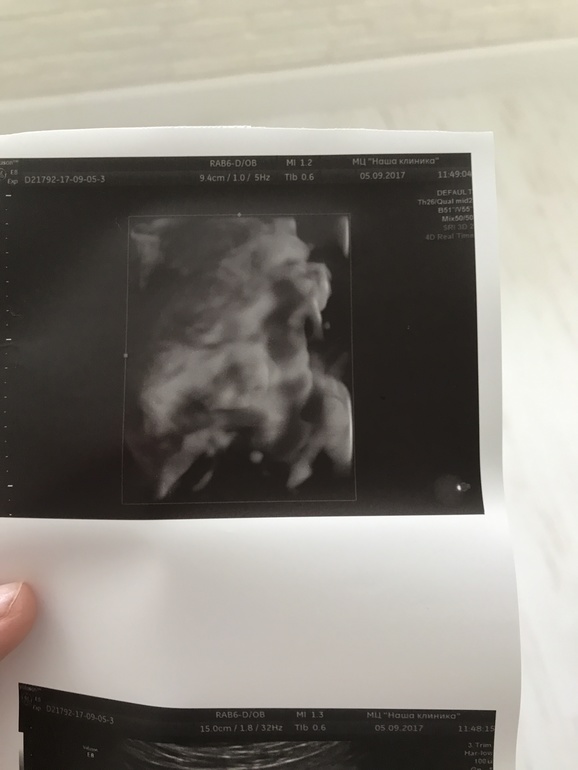

Ну и новости с полей,так сказать) прибавка в весе 8,5 кг,чувствую себя хорошо,только стало тяжеловато ходить на дальние расстояния. Во вторник были на УЗИ,малыш сел на попу,до этого был в головном,поэтому и изменились шевеления,раньше в верхней части живота активные были,а тут больше внизу шевелился,начала стоять в колено-локтевой позе и снова стал бить под рёбра,может опять кувыркнулся головкой вниз.Также сыночек нам показал личико наконец-то и почти не закрывал ручками, много зевал,а потом улыбнулся,наше солнышко так любим его уже. На первом снимке видно очертание лица уже👶🏼